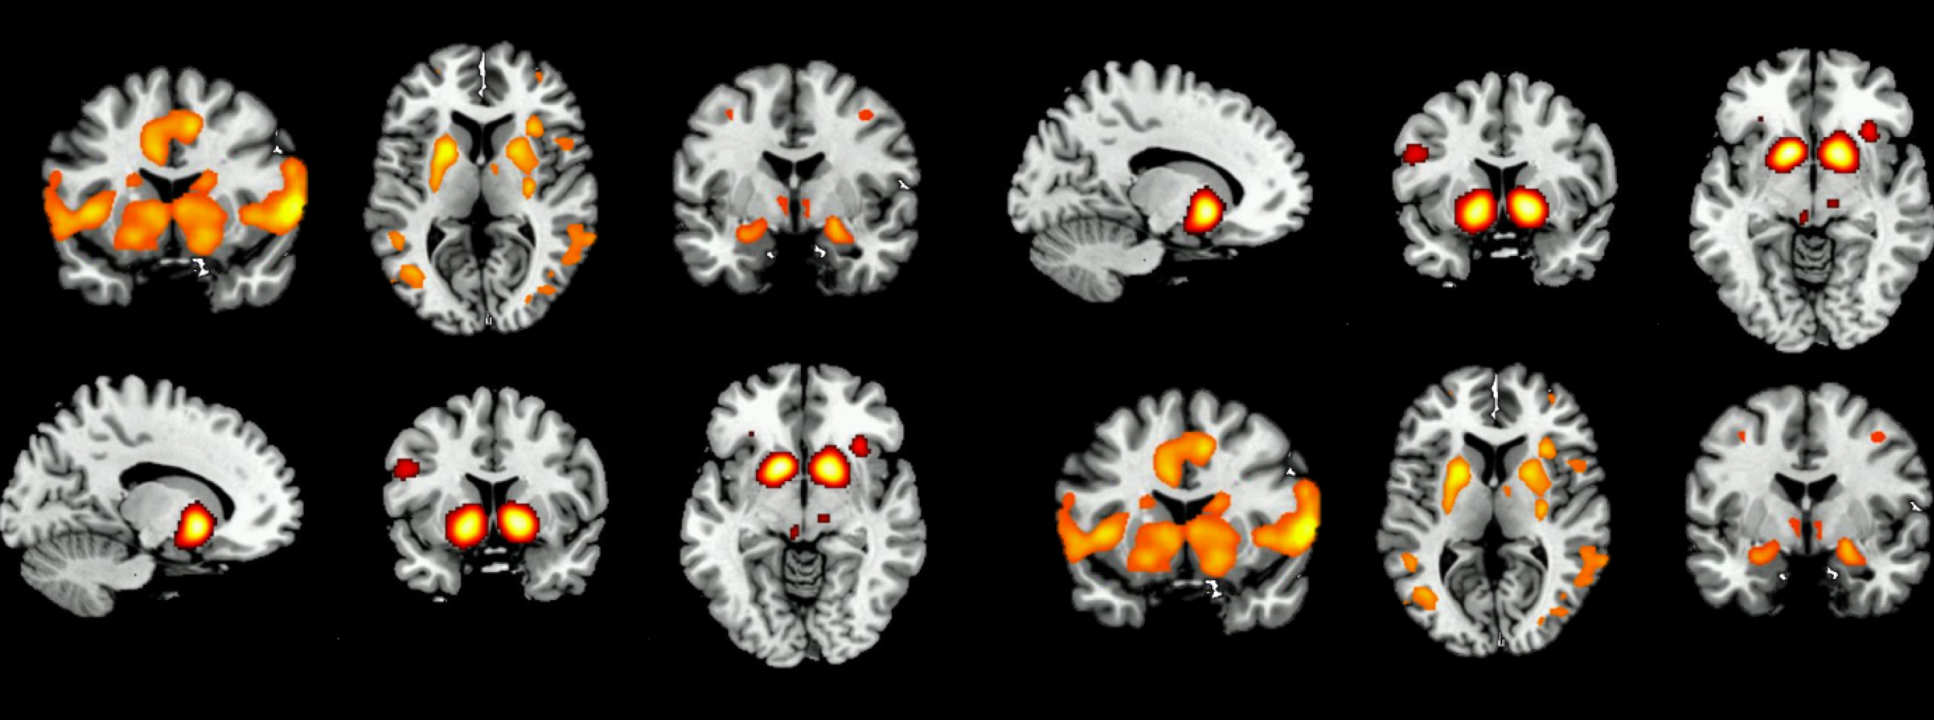

Our research uses brain-imaging techniques to detect subtle changes in brain function while performing psychological tasks. These tasks measure brain processes that are important in opioid dependence. We will investigate the effects of aprepitant (for further information, please see Aprepitant Information (.pdf)) on brain function in opioid-dependent individuals during methadone treatment, and again, after achieving abstinence from methadone.